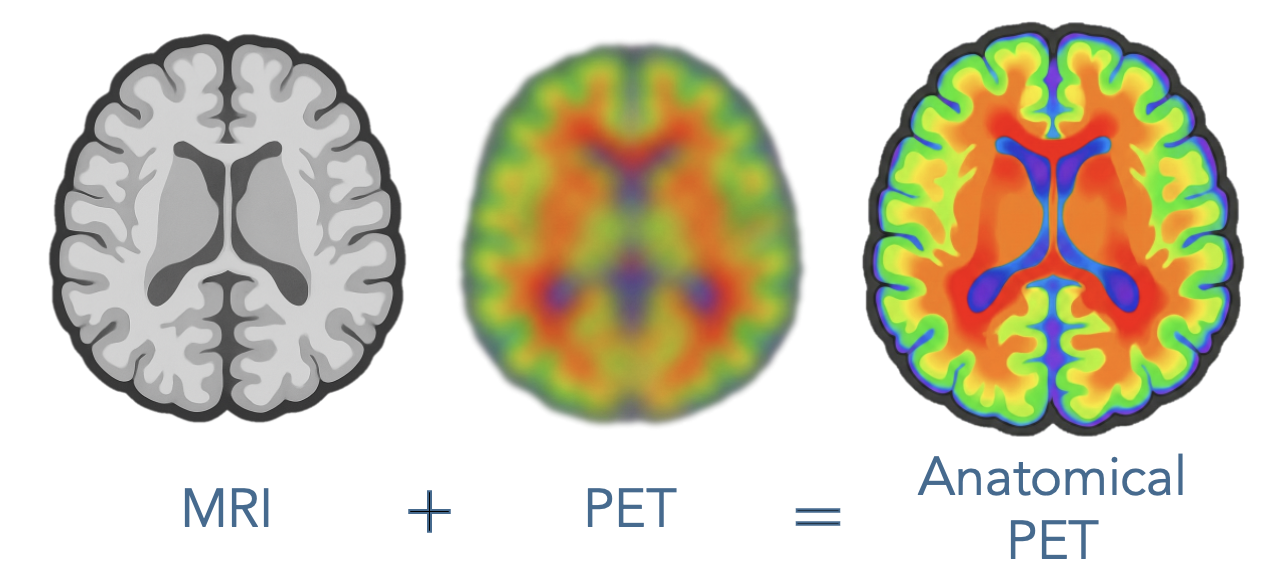

Solution: Transform aging PET fleets into Anatomical PET with MICSI-PET.

MICSI-PET is a turnkey upgrade that dramatically enhances PET image quality by using the MRI as an anatomical guide. This process does not require any additional imaging as all patients should have received an MRI prior to amyloid PET imaging. Operationally, this upgrade removes the primary barrier for scaling Alzheimer’s therapies by (1) enabling high-end PET imaging on low-end or aging PET scanners; (2) enabling shorter PET examinations leading to greater throughput; (3) minimizing ambiguity of positive/negative amyloid PET imaging by showing clearer boundaries between gray and white matter: